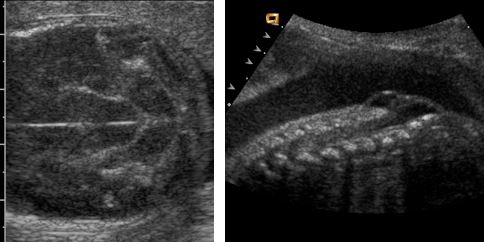

Figure 4.2. All three images show varying degrees of vermian agenesis. In every case, the cisterna magna is clearly large and > 10 mm. The cisterna magna also communicates with the 4th ventricle.

You will notice that in the three cases in figure 4.2, the cisterna magna is visually abnormal and all measure larger than 10 mm and the cerebellar vermis is absent.